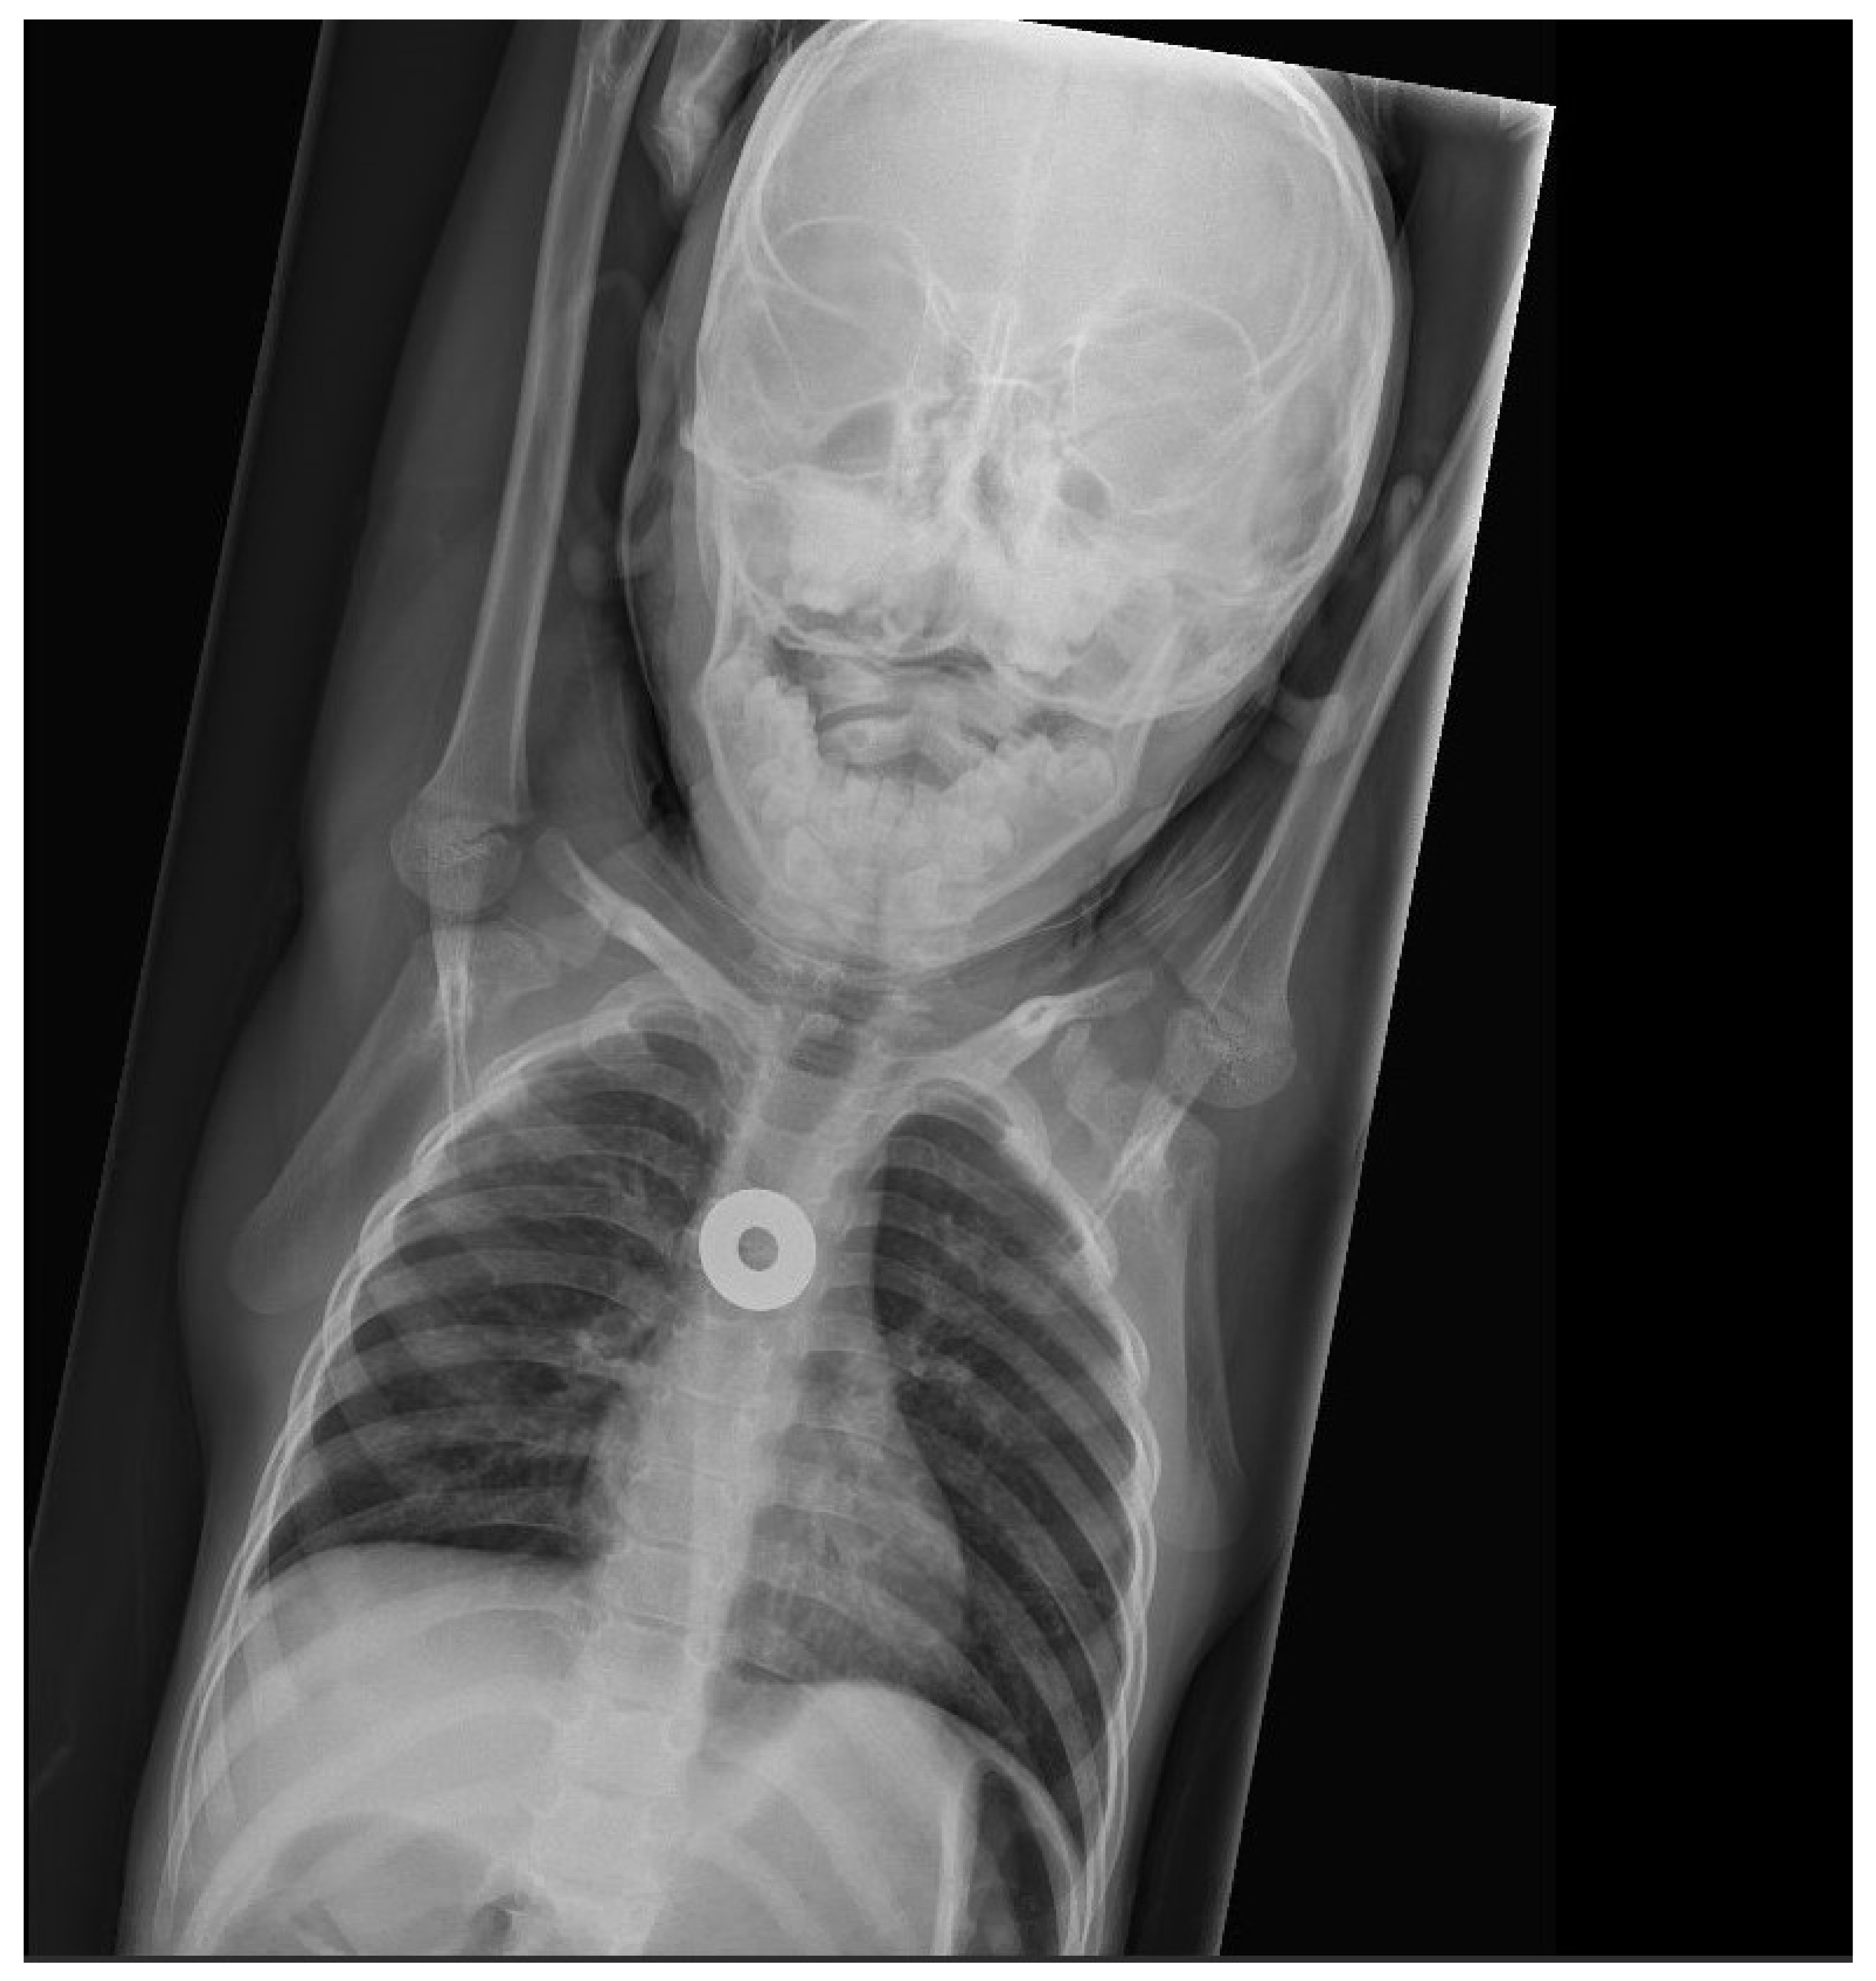

Coins are, by far, the swallowed foreign bodies most commonly brought to medical attention [8]. Thus, there has been substantial literature on coin ingestion. In the United States, children swallow far more pennies than other coins [21]. While the majority pass through the GI tract without complication, it is not uncommon for a previously healthy child to have a swallowed coin lodge in the esophagus. About 70% of coins (and similarly-shaped objects) lodge at the upper esophagus, corresponding to the area between the clavicles on frontal radiographs (Figure 1) [21]. The remainder are found lodged with about equal frequency in the mid-esophagus (Figure 2) or at the lower esophageal sphincter (Figure 3). While one-third to one-half of coins in the mid-esophagus or at the lower esophageal sphincter will pass into the stomach spontaneously in minutes to hours, especially in conjunction with oral intake, it is less common for upper esophageal coins to progress spontaneously [21]. Coins that lodge in the esophagus may partially or completely obstruct the esophagus, causing inability to swallow, or cause complications due to local pressure necrosis on the esophageal mucosa. While coins may remain in the esophagus for long periods, even years, with minimal symptoms, some migrate into the mediastinum or structures of the chest, including the aorta, with important morbidity, such as mediastinitis or creation of an aorto-esophageal fistula [8]. Occasionally, a radiograph performed in evaluation of cough, fever, dysphagia, failure to thrive, or other complaint will reveal an unexpected esophageal coin. It is often difficult to determine how long the coins have been in place. These coins may be associated with esophageal scarring, and/or have migrated into other chest structures [8]. Management will require subspecialty consultation, and likely endoscopic or surgical removal.

Figure 1.

Chest radiograph showing a coin lodged in upper esophagus. Details suggesting it is a United States dime are visible on close inspection (photo courtesy of Timothy Johnson, DO, MMM).